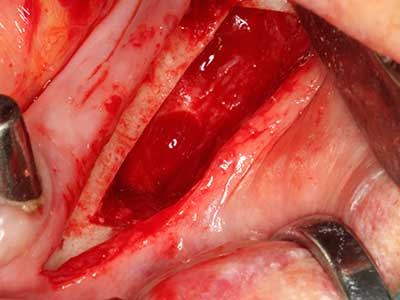

Bei der Knochenblockentnahme zeigen sich weitere Vorteile für die Piezochirurgie: Neben der bereits beschriebenen hohen Präzision bei der Osteotomie stellt sich gerade die Verwendung der dünnen Sägespitzen als besonders materialschonend heraus. Bei der Verwendung insbesondere von Lindemannfräsen sind mit deutlich höheren Entnahmeverlusten durch die dickere Instrumentenspitze zu rechnen (Lakshmiganthan, Gokulanathan et al. 2012). Die insbesondere bei retromolar entnommenen Blocktransplantaten notwendige basale Abtrennung wird durch speziell hierfür vorgesehene rechtwinklige Sägen erleichtert, so dass die Piezochirurgie als präzises, übersichtliches und sicheres Verfahren zur retromolaren Knochenblockgewinnung angesehen wird (Happe 2007) (Abb. 1-12).

Autogene Knochentransplantate finden als Blöcke, Schalen, Ringe und gerade in der Kombination mit Knochenersatzmaterialien als Späne Anwendung. Wird gleichzeitig mit der Augmentation ein Implantatbett aufbereitet, so haben sich zur Sammlung der anfallenden Knochenspäne verschiedene Knochenfiltersysteme bewährt. Alternativ kann eine niedrigtourige Implantatbettpräparation ohne Wasserkühlung erfolgen. Wird kein Implantat inseriert, so lassen sich mit Bone Scrapern Knochenspäne aus der Peripherie gewinnen. Ebensolches ist auch mit speziellen Ansätzen mittels Piezochirurgie möglich, wobei sich in einer eigenen Studie im direkten Vergleich zu mit Rosenbohrern gewonnenen Spänen eine bessere Qualität für die Piezospäne nachweisen ließ (Chiriac, Herten et al. 2005).